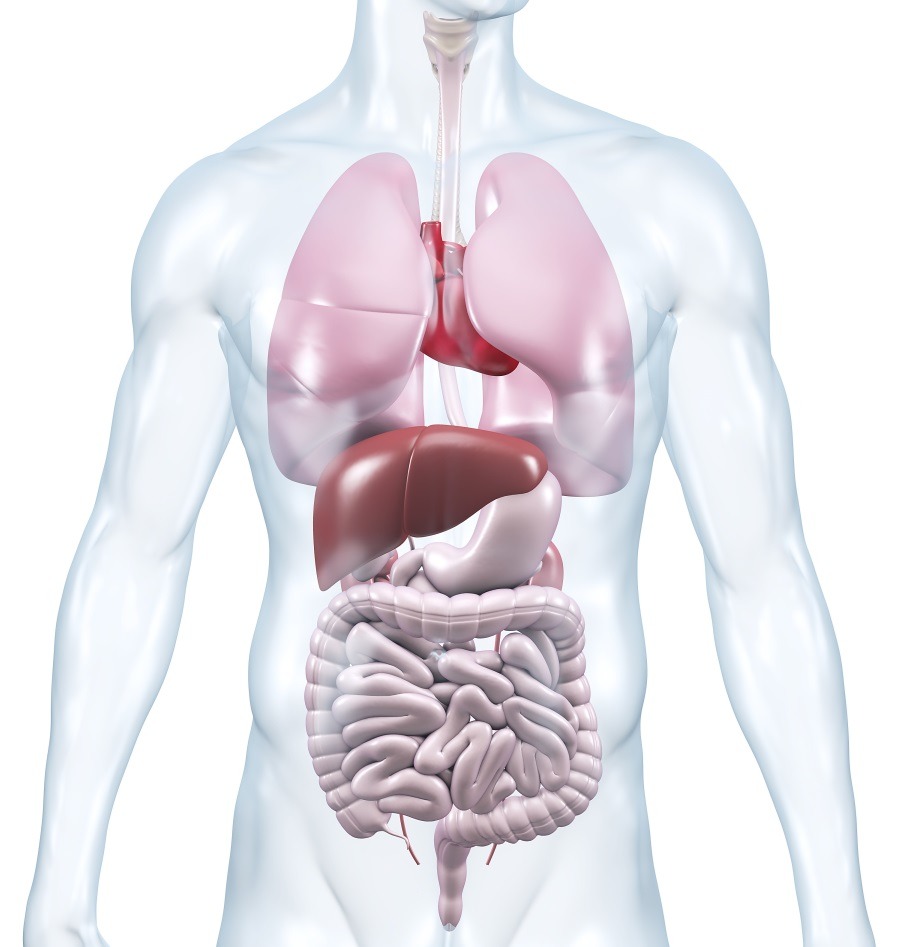

Изображения и визуализация внутренних органов человека